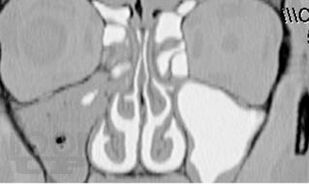

Представлены данные об этиологии, патогенезе, классификации форм хронического синусита. Приведен обзор современных методов диагностики и лечения. Обсуждается консервативное лечение синуситов с учетом особенностей микрофлоры, освещены не только стандартные хирургические подходы, но и некоторые базовые и прикладные вопросы функциональной эндоскопической риносинусохирургии.